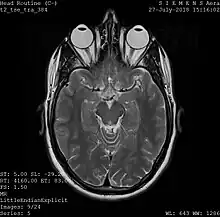

Magnetic resonance imaging

A magnetic resonance imaging instrument (MRI scanner), or "nuclear magnetic resonance (NMR) imaging" scanner as it was originally known, uses powerful magnets to polarize and excite hydrogen nuclei (i.e., single protons) of water molecules in human tissue, producing a detectable signal which is spatially encoded, resulting in images of the body.[5] The MRI machine emits a radio frequency (RF) pulse at the resonant frequency of the hydrogen atoms on water molecules. Radio frequency antennas ("RF coils") send the pulse to the area of the body to be examined. The RF pulse is absorbed by protons, causing their direction with respect to the primary magnetic field to change. When the RF pulse is turned off, the protons "relax" back to alignment with the primary magnet and emit radio-waves in the process. This radio-frequency emission from the hydrogen-atoms on water is what is detected and reconstructed into an image. The resonant frequency of a spinning magnetic dipole (of which protons are one example) is called the Larmor frequency and is determined by the strength of the main magnetic field and the chemical environment of the nuclei of interest. MRI uses three electromagnetic fields: a very strong (typically 1.5 to 3 teslas) static magnetic field to polarize the hydrogen nuclei, called the primary field; gradient fields that can be modified to vary in space and time (on the order of 1 kHz) for spatial encoding, often simply called gradients; and a spatially homogeneous radio-frequency (RF) field for manipulation of the hydrogen nuclei to produce measurable signals, collected through an RF antenna.

Like CT, MRI traditionally creates a two-dimensional image of a thin "slice" of the body and is therefore considered a tomographic imaging technique. Modern MRI instruments are capable of producing images in the form of 3D blocks, which may be considered a generalization of the single-slice, tomographic, concept. Unlike CT, MRI does not involve the use of ionizing radiation and is therefore not associated with the same health hazards. For example, because MRI has only been in use since the early 1980s, there are no known long-term effects of exposure to strong static fields (this is the subject of some debate; see 'Safety' in MRI) and therefore there is no limit to the number of scans to which an individual can be subjected, in contrast with X-ray and CT. However, there are well-identified health risks associated with tissue heating from exposure to the RF field and the presence of implanted devices in the body, such as pacemakers. These risks are strictly controlled as part of the design of the instrument and the scanning protocols used.

Because CT and MRI are sensitive to different tissue properties, the appearances of the images obtained with the two techniques differ markedly. In CT, X-rays must be blocked by some form of dense tissue to create an image, so the image quality when looking at soft tissues will be poor. In MRI, while any nucleus with a net nuclear spin can be used, the proton of the hydrogen atom remains the most widely used, especially in the clinical setting, because it is so ubiquitous and returns a large signal. This nucleus, present in water molecules, allows the excellent soft-tissue contrast achievable with MRI.[6]

A number of different pulse sequences can be used for specific MRI diagnostic imaging (multiparametric MRI or mpMRI). It is possible to differentiate tissue characteristics by combining two or more of the following imaging sequences, depending on the information being sought: T1-weighted (T1-MRI), T2-weighted (T2-MRI), diffusion weighted imaging (DWI-MRI), dynamic contrast enhancement (DCE-MRI), and spectroscopy (MRI-S). For example, imaging of prostate tumors is better accomplished using T2-MRI and DWI-MRI than T2-weighted imaging alone.[7] The number of applications of mpMRI for detecting disease in various organs continues to expand, including liver studies, breast tumors, pancreatic tumors, and assessing the effects of vascular disruption agents on cancer tumors.[8][9][10]